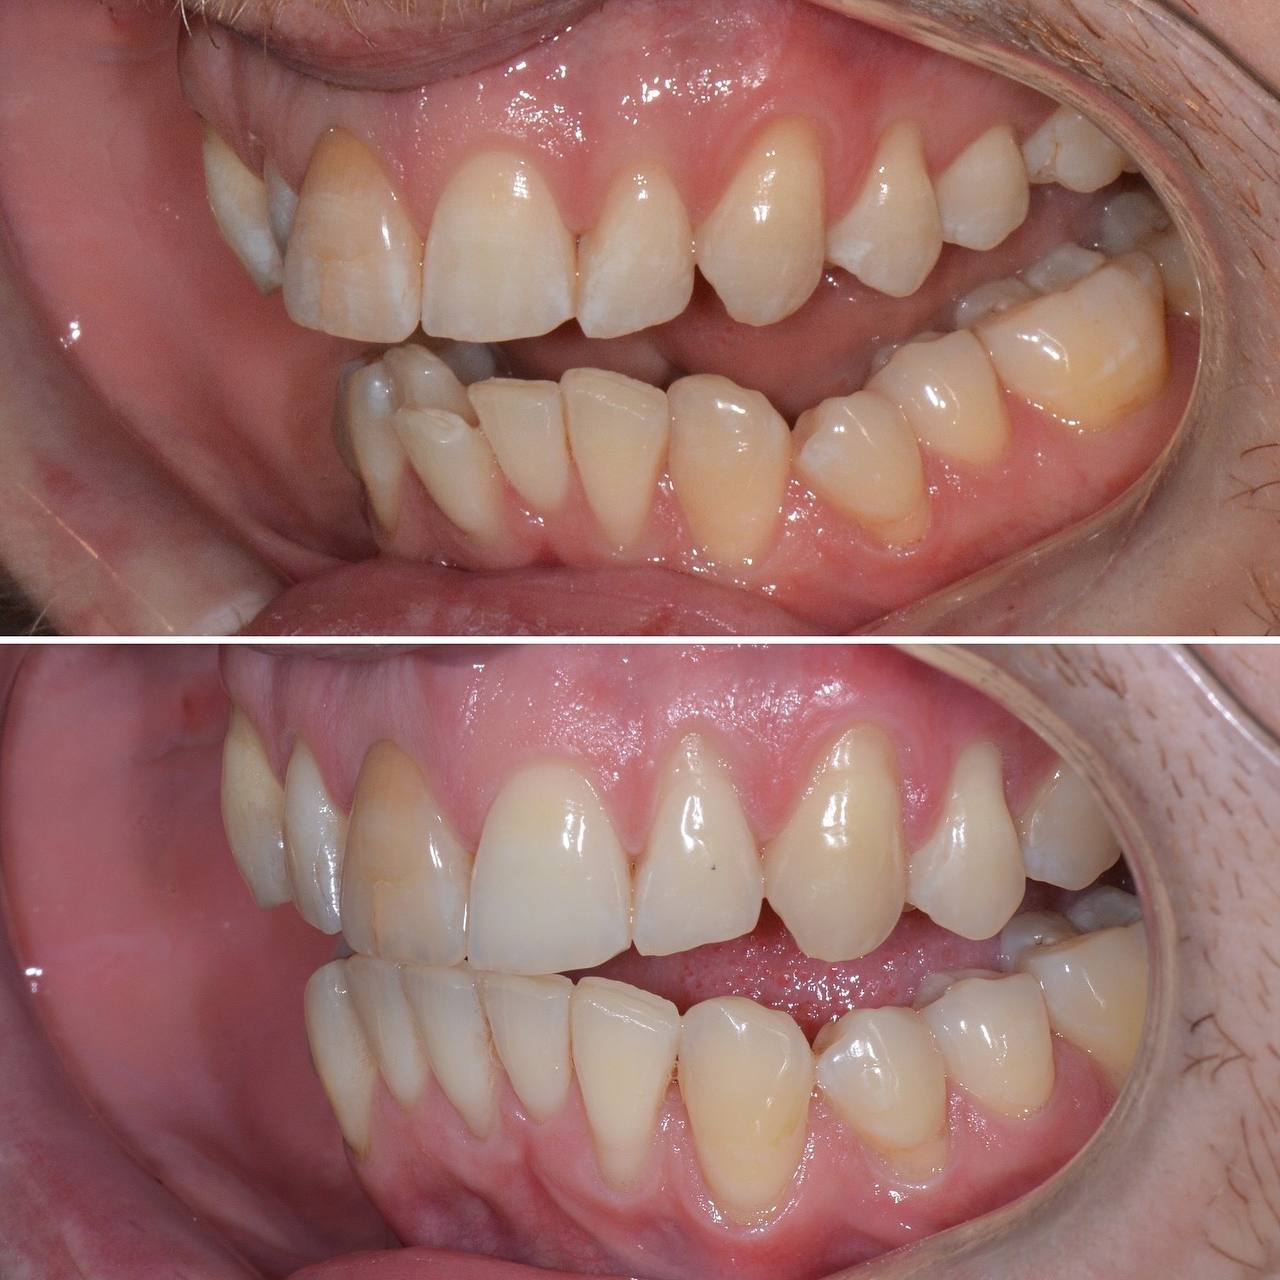

К нам с стоматологию обратился пациент с желанием сделать улыбку красивее. Лечением занимался стоматолог-ортодонт. Прикус и кривизну зубов исправляли при помощи элайнеров. Лечение заняло 12 месяцв. За это время было использовано 30 комплектов элайнеров.

Фото до и после лечения зубов элайнерами